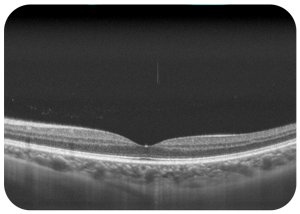

光学相干断层扫描